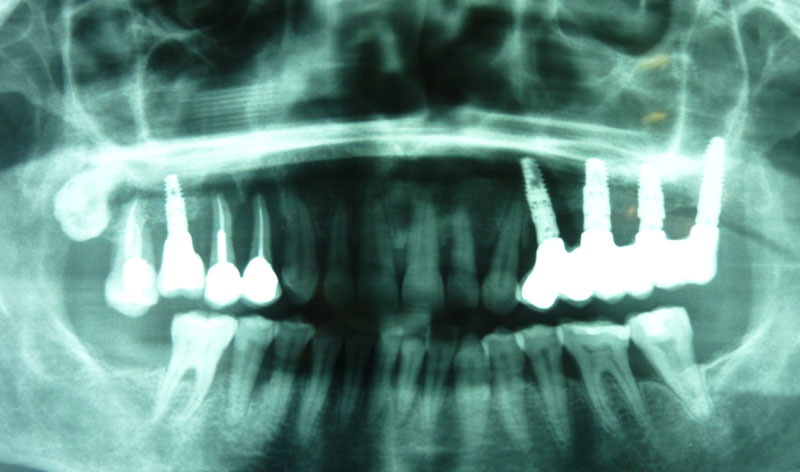

Se trata de una intervención que se efectúa bajo anestesia local. Está indicada en aquellos casos que requieren la colocación de implantes en el área posterior del maxilar superior donde el paciente no tiene el hueso suficiente para asegurar la fijación de los implantes.

Una vez realizada la intervención, en algunos casos se pueden colocar los implantes a la misma vez y en otros, es necesario esperar seis meses para que el material óseo forme un hueso con buena calidad que asegure el éxito de los implantes.